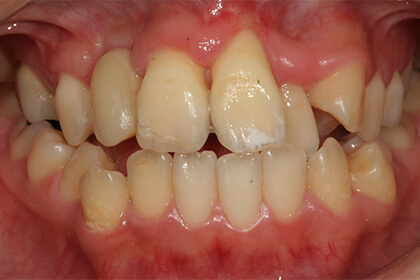

Before

総合的な審美治療

After

基礎データ 30代女性

治療期間 2003〜2009年

治療費 144万(矯正治療の費用は他院にて請求)

主な治療 歯列矯正・抜歯・軟組織移植・クラウンブリッジ補綴

治療計画 不正なクラウンを除去、保存できない歯を抜歯し、正しい噛み合わせを作れるように外科矯正を含んだ矯正治療を行う。

矯正治療後、前歯部の吸収した組織を増大し、クラウンブリッジを作成した。